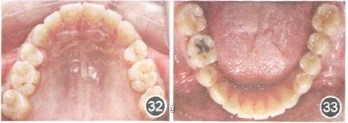

移植牙牙周情况正常、无异常松动度、无根尖症状,咀嚼功能良好。x线片显示,上前牙回收显著,移植牙牙周膜问隙正常,硬骨板形成,无根尖病变。(摘自《中华口腔医学杂志》)